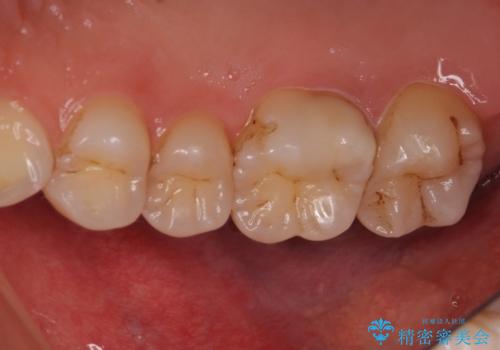

PGA(ゴールド)インレー しみる歯の治療